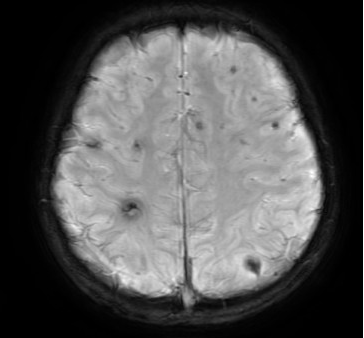

图一   心脏超声显示二尖瓣大量反流                                   图二 左侧腘动脉以下闭塞

通常这种情况下想保住二尖瓣很难,本可以按照计划将二尖瓣换成机械瓣,但考虑以后孩子要长期服药,还有面临二次手术风险的可能。“我们还是尽量让他使用自己的瓣膜,不要给孩子留下遗憾!”这样的信念使得崔晓征毫不犹豫地再次打开洋洋的心脏,对二尖瓣进行了二次修复。心脏再次复跳后,超声显示瓣膜干干净净,反流几乎完全消失,洋洋的二尖瓣保住了!。